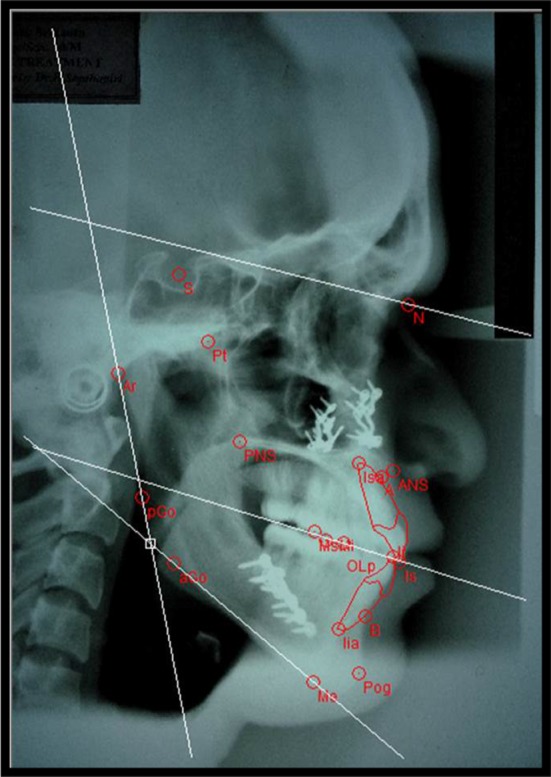

Fig. 2.

Post-treatment COGS hard tissue